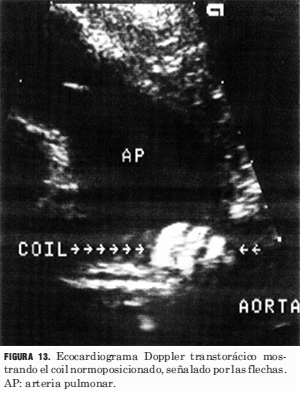

Los procedimientos de cierre del ductus se llevaron a cabo sin el uso simultáneo del ecocardiograma (figuras 9, 10, 11, 12 y 13).

Figura 13. Ecocardiograma Doppler transtorácico mostrando el coil normoposicionado, señalado por las flechas. AP: arteria pulmonar.